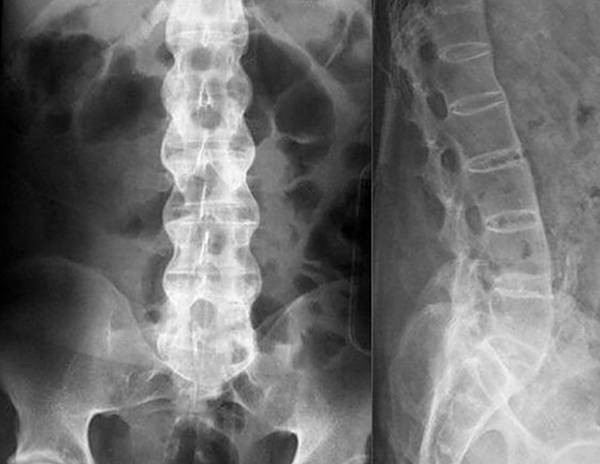

Если симптомы указывают на грыжу, остеохондроз или радикулит, для диагностики обычно используют рентгенографию. Этот метод прост и доступен, а время на получение снимка минимально, в отличие от компьютерной томографии (КТ), где требуется длительное неподвижное состояние пациента. Для оценки состояния сосудов и мягких тканей назначают УЗИ, а при подозрении на инфекцию проводятся лабораторные исследования крови и мочи. На основе полученных результатов врач подбирает оптимальный метод лечения.

При заболеваниях позвоночника чаще всего используют рентгенографию для диагностики.